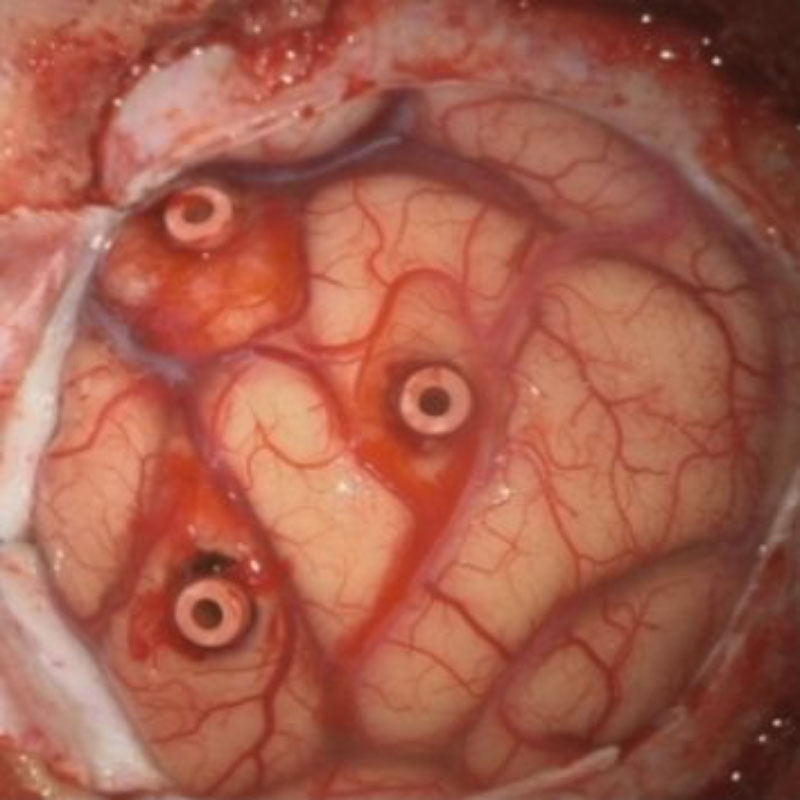

右頭頂葉腫瘍

頭蓋内腫瘍摘出術

No.’25_108 摘出 前

No.’25_108  摘出 中

No.’25_108 摘出 後